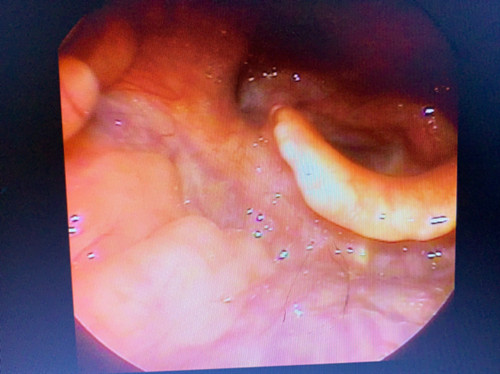

相关检查:间接喉镜、显微或电子喉镜检查,可发现位于会厌部位的类圆形或半球形肿物,表面光滑,蒂部广,可呈灰白、浅黄或淡红色。

手术治疗:会厌囊肿以手术治疗为主,在支撑喉镜下将舌根撑起,充分暴露会厌囊肿,用喉刀、剪、和杯状钳将囊肿外侧壁切除。也可用激光、等离子刀将其切除。对于较大的囊肿,可以先将囊肿中的液体抽出大部分,再用上述方法切除。年老体弱者,将囊肿中的液体抽吸干净后,还可注射适量的无水酒精至囊腔中使其内外侧囊壁粘连,加速其愈合。该病预后较好,通过手术切除可以根治,一般不易复发。药物治疗:术后予以抗生素以减轻喉水肿,避免继发感染;也可予低剂量激素经口雾化给药,以缓解黏膜水肿。